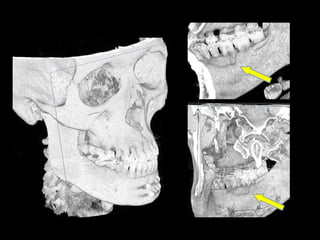

TC 3D

Adquisición de datos Reconstrucción virtual del modelo 3D Validación Validación Producción física del modelo Cirugía de modelo: moldeo placa, osteotomía mandíbula y peroné Esterilización: placa y modelo Uso en quirófano

Hiperplasia condílea dcha

Anquilosis ATM dcha